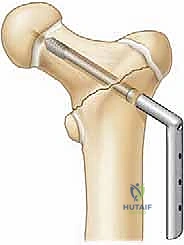

3. التثبيت الداخلي (Internal Fixation)

تُستخدم أدوات تثبيت خاصة بالأطفال. في الأطفال الأكبر سناً، تُستخدم مسامير مجوفة (Cannulated Screws) يتم إدخالها بدقة فائقة. يحرص الدكتور هطيف بصرامة على عدم اختراق صفائح النمو بالمسامير إلا إذا كانت الضرورة القصوى تقتضي ذلك (وفي هذه الحالة تُستخدم مسامير ملساء لتجنب إعاقة النمو).